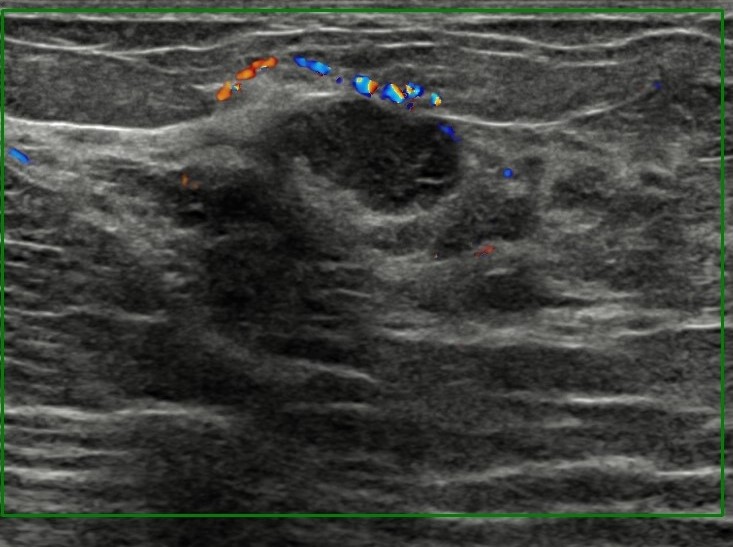

The most common cause of skin metastases in adult women is primary breast carcinoma, which comprises about 70% of cases [1]. Skin metastases have non-specific clinical appearances, making it challenging to differentiate them from other benign conditions [1]. We present a case of a 52-year-old female with type II diabetes and a three-month history of refractory skin lesions who did not respond to anti-inflammatory treatment. The patient subsequently complained of a right breast lump, evaluation of which led to the diagnosis of bilateral synchronous invasive lobular carcinoma.